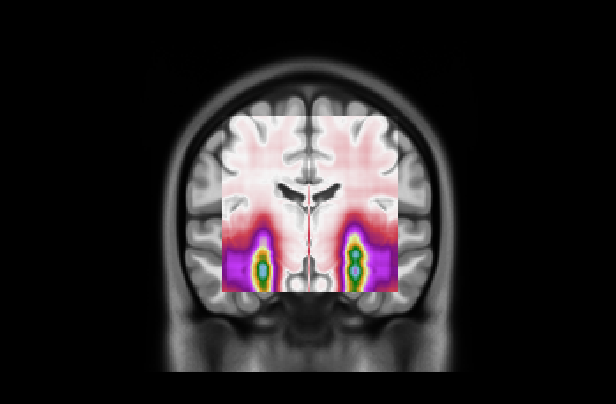

(a) Axial

Refer to caption

(b)

(c) Coronal

(d) Fold 1

(e) Sagittal

Figure 5: Average attention weight distributions generate by our model for each fold and each plane

Fig. 5 presents our diagnosis network’s average attentional weight distributions for each fold in the axial, coronal, and sagittal views. Upon examination of the histograms for each view, we observe a remarkable consistency in the distribution shapes across all five folds, indicating that our interpretability approach is stable despite the variation in the train/test set data. Specifically, the axial distributions reveal a consistent concentration of attentional weights around the initial slices. This trend suggests the model’s recurrent focus on the brain’s inferior regions, notably the areas where degenerative changes first manifest in AD, such as the hippocampus. In the coronal view, attentional weights are notably centered, indicating that the model consistently identifies the central part of the brain as significant. This central focus might correspond to the medial temporal lobe, including the hippocampus and the surrounding regions, further substantiating the axial findings. The sagittal view is the only bimodal distribution, suggesting that the model pinpointed symmetrical areas along this plane. We hypothesize that the network was focusing on the hippocampus since it adheres to all the constraints: situated in the inferior part of the brain, centrally located, and symmetrical. The consistency and specificity of these findings across multiple data folds strengthen the argument that our network could reliably identify specific brain regions as a critical biomarker for distinguishing between AD and CN subjects.